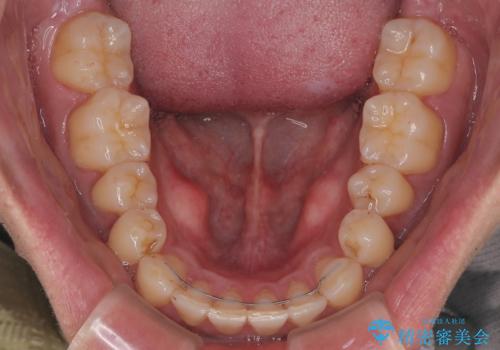

矯正治療後は、後戻りを防ぐために リテーナー(保定装置) を使用していただきます。

以前の矯正で後戻りを経験されているため、患者様にも重要性をご理解いただき、

しっかりと保定していただくことで美しい歯並びを長く維持できます。